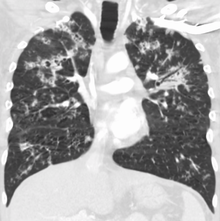

Tuberculosis of the lungs

Testing for miliary tuberculosis is conducted in a similar manner as for other forms of tuberculosis, although a number of tests must be conducted on a patient to confirm diagnosis.[5] Tests include chest x-ray, sputum culture, bronchoscopy, open lung biopsy, head CT/MRI, blood cultures, fundoscopy, and electrocardiography.[11] The tuberculosis (TB) blood test, also called an Interferon Gamma Release Assay or IGRA, is a way to diagnose latent TB. A variety of neurological complications have been noted in miliary tuberculosis patients—tuberculous meningitis and cerebral tuberculomas being the most frequent. However, a majority of patients improve following antituberculous treatment. Rarely lymphangitic spread of lung cancer could mimic miliary pattern of tuberculosis on regular chest X-ray. [16]